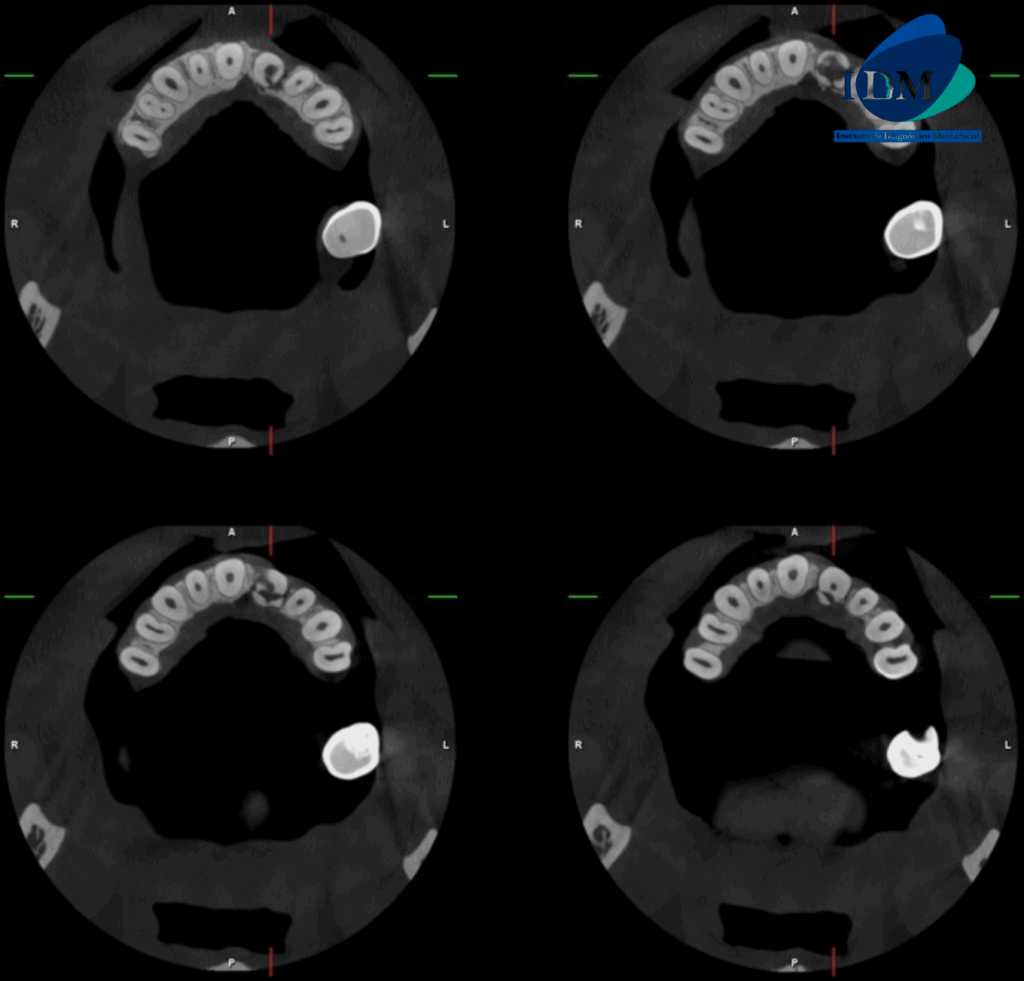

A la evaluación de la tomografía volumétrica (CBCT) en los cortes axiales (Figura 2) y transaxiales (Figura 3), se aprecia trazo hipodenso horizontal a nivel del tercio cervical radicular ocasionando separación de dos fragmentos

CORTES AXIALES

CASO 315 IDM cortes axiales